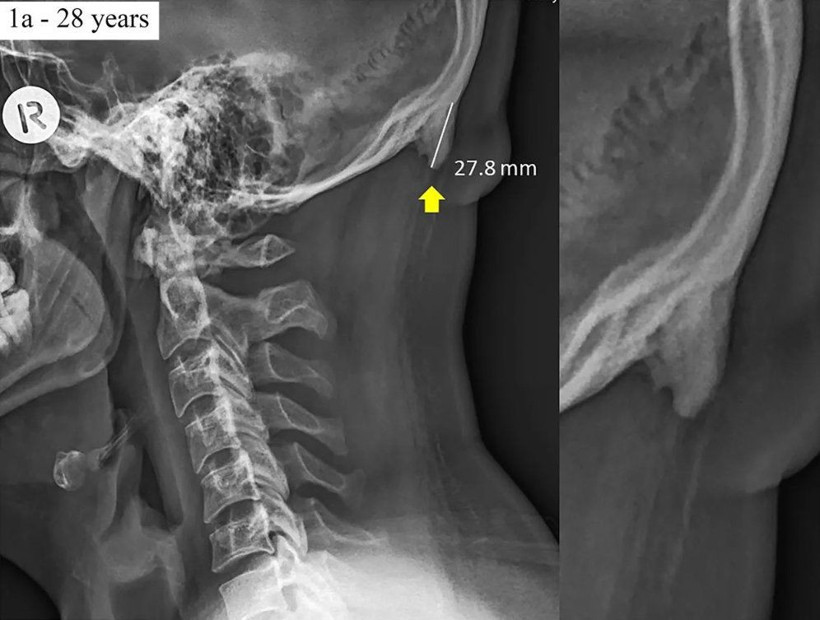

Avustralya’daki Sunshine Coast Üniversitesi’den bilim adamları Dr. David Shahar ve Prof. Mark Sayers, 18-30 yaş arasındaki 218 kişinin röntgen çekimlerini inceledi. Yapılan araştırmalar sonucu röntgen çekilen kişilerin neredeyse yarısının kafatası şeklinin yoğun cep telefonu ve tablet kullanımına bağlı olarak ‘değiştiği’, boynuzumsu bir çıkıntıya benzediği belirtildi.

Yapılan araştırmaya göre, gününün büyük kısmında teknolojik aletlere kafasını eğerek bakan gençlerin, kafatasındaki oksipital kemik denen bölge, görünür şekilde belirginleşmeye başlıyor.

10 yıldır gözlemleniyor

Bilim adamı David Shaharr, 20 yıldır klinik tedavi uzmanı olduğunu belirterek “Ancak sadece son 10 yıldır hastalarımın kafatasındaki büyümeyi gözlemliyorum” açıklamasını yaptı.